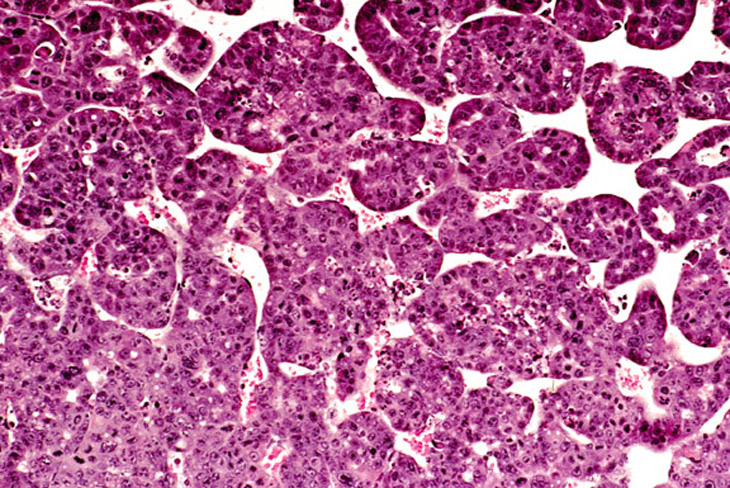

Cholangiocarcinoma next to a more adenomatous lesion with hepatocyte cytological features in a 4-week-old transgenic mouse.